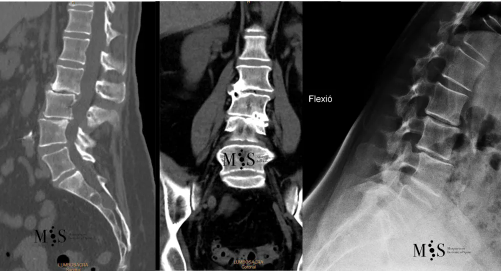

Figures showing the case of a female patient with a degenerative scoliosis (image in the middle) and an instability on lumbar levels L2/L3 and L3/L4 (note the "step" between the vertebrae on the images at the left and right) that require OLIF surgery for correction.